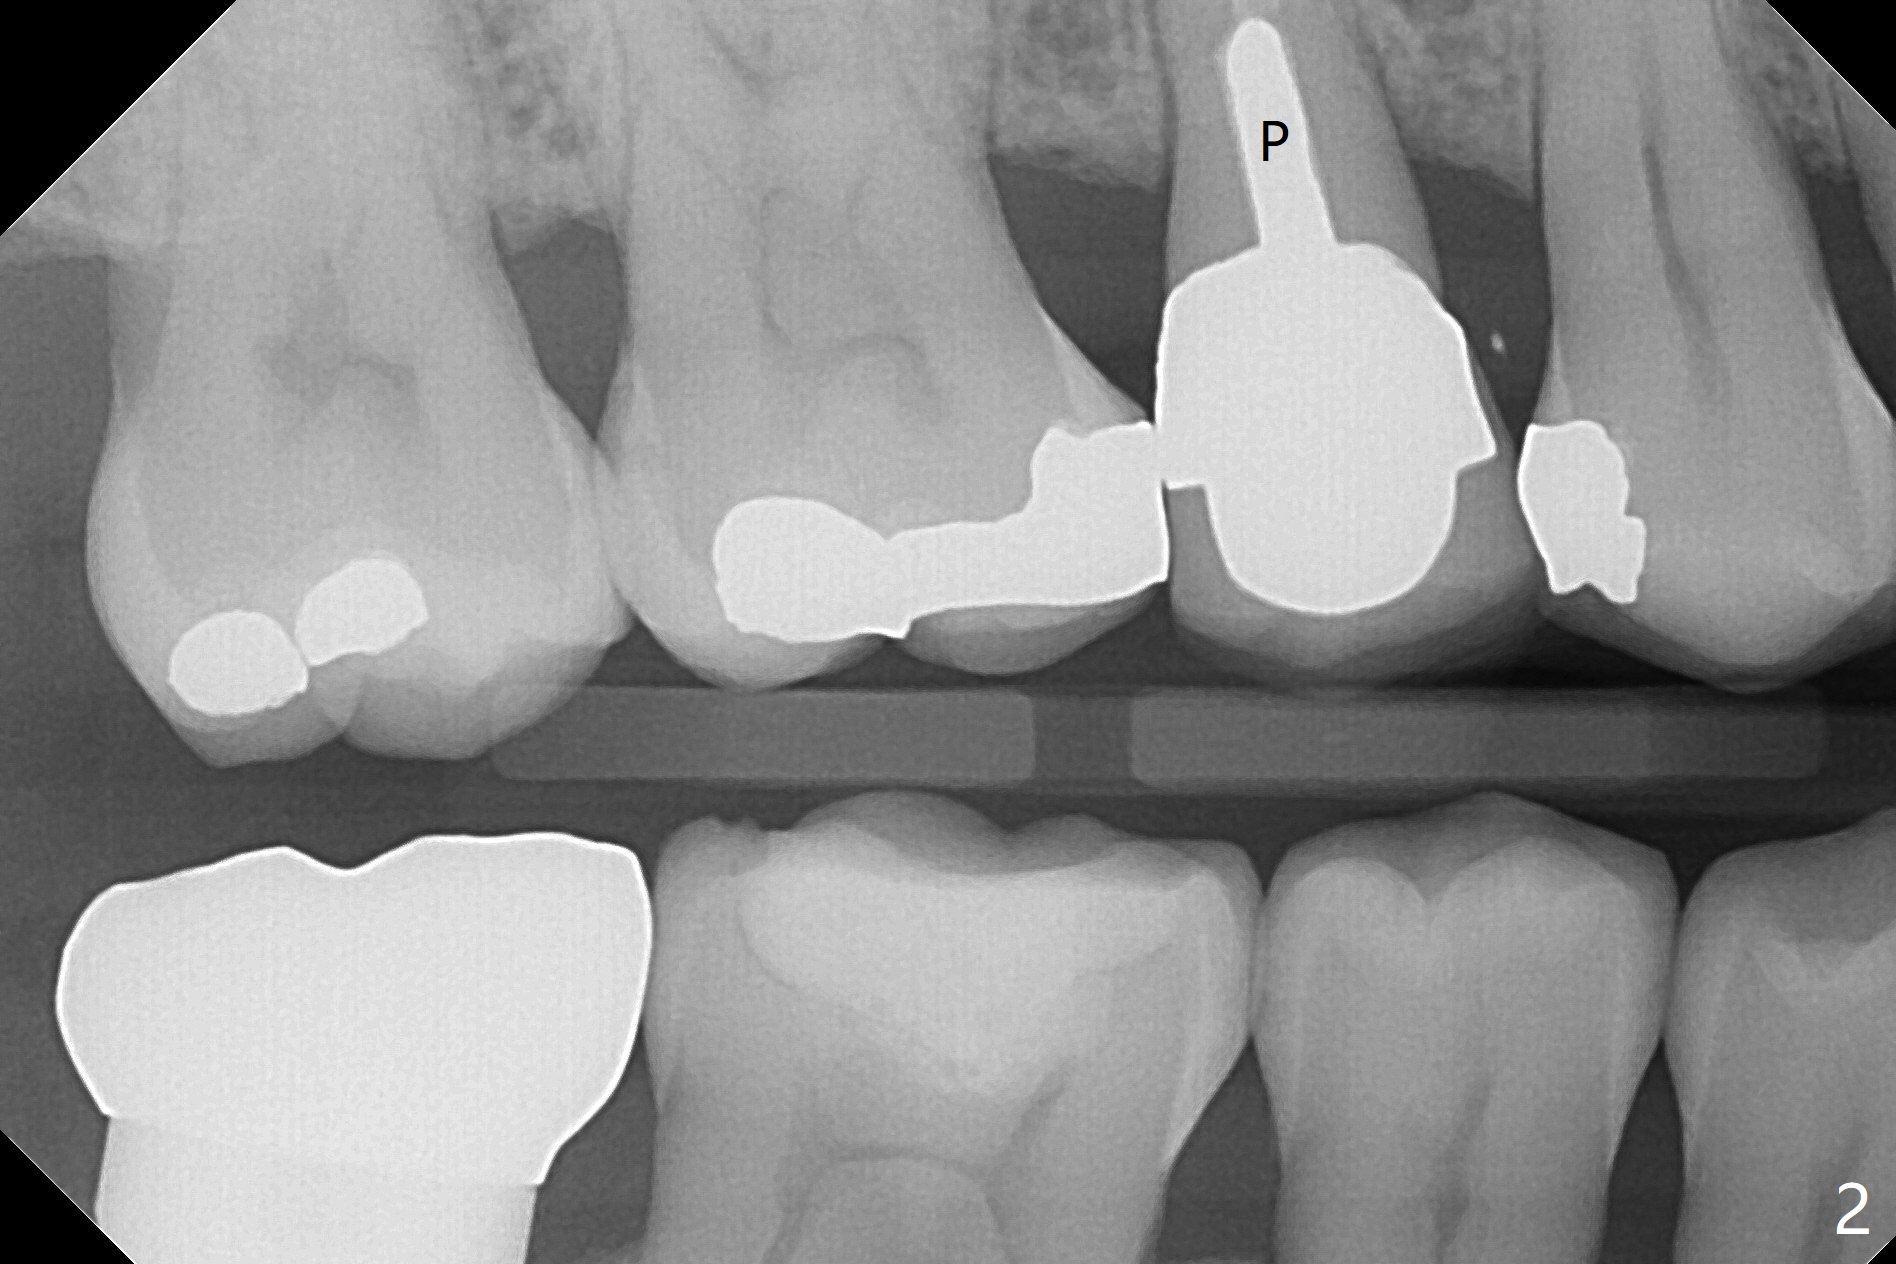

A 48-year-old man has had palatal and buccal abscesses at #4 for 6 and 1 months, respectively (Fig.1). The patient loves bubble gums. There is a post at #4 (Fig.2). CBCT shows apical buccal and palatal defects (Fig.3,4). There are no deep periodontal pockets. The tooth has mobility II. No guide is fabricated so that we have options to do bone graft or immediate implant after extraction, depending on extent of bone defects. Later impression is taken for guide. Use UF implant 4.5x10 mm with sinus lift (PRF membranesx2).